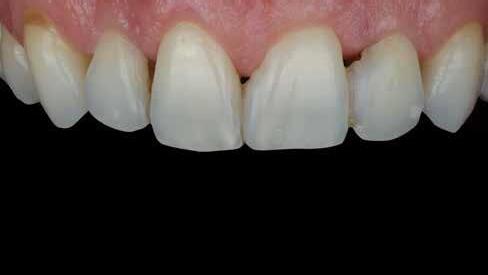

Egy 30 éves, negatív kórtörténettel rendelkező beteg azzal a kéréssel fordult hozzánk, hogy cseréljük ki az UR1 traumája után, 10 évvel korábban készült korábbi kompozit-helyreállítást.

A klinikai vizsgálat során az UR1 reagál a viabilitási tesztre, és az ugyanazon a napon készült röntgenfelvételen nem mutat periapikális elváltozásokat (1. ábra).

Az UR1 elszíneződött, és palatálisabb helyzetben van, mint az ellenoldali központi UL1 (2. ábra)

Az esztétikai elemzés a gingivális zenit aszimmetriáját mutatja az UR1 és az UL1 között. Parodontális szonda segítségével, plexusérzéstelenítés után, az IA

típusú funkcionális hám megváltozott passzív erupcióját igazoljuk Coslet és mtsai. osztályozása szerint (3. ábra)

A lehető legkonzervatívabb helyreállító kezelés elvégzése érdekében a páciensnél, figyelembe véve a megtartott fogelem korát és vitalitását, a tervezés és a diagnosztikai felviaszolás után a közvetlen kompozit-helyreállítás elvégzése mellett döntünk.

A pácienst 21 nap (14–15. ábrák) és 12 hónap (16. ábra) után ismét ellenőrizzük, hogy értékeljük az esztétikai eredményt a forma és a szín tekintetében.